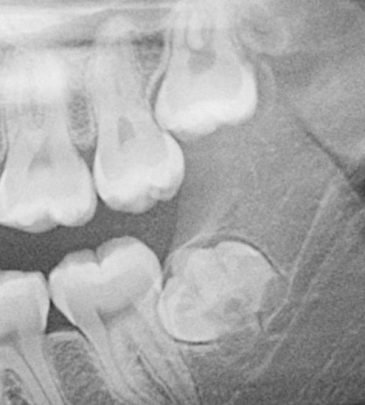

Our team of reputed dental practitioners is committed to ensuring that our courses are relevant, engaging, and reflect the latest advances in dentistry. Our wealth of clinical experience is leveraged through the collaborative effort in teaching fundamental concepts to advanced procedures in restorative dentistry, implantology, orthodontics, and periodontics.